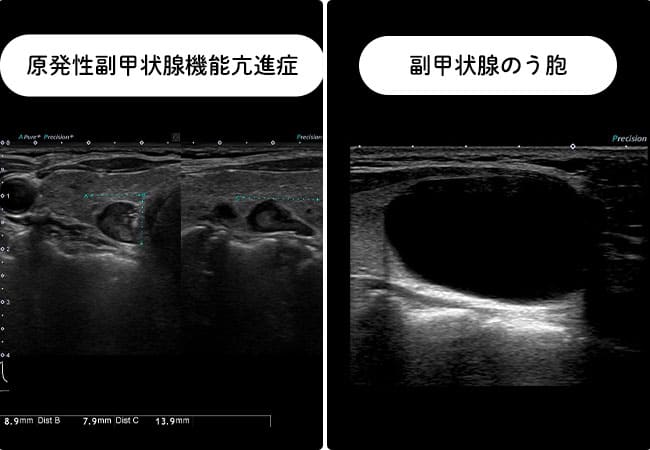

⑤副甲状腺腺腫、副甲状腺のう胞

甲状腺のしこりの鑑別として、甲状腺の背側にある副甲状腺の病気が挙げられます。正常の副甲状腺はエコーでは描出できませんが、腫瘍、のう胞などでは甲状腺のしこり、のう胞と鑑別を要します。

血液検査で、副甲状腺ホルモン過剰分泌をしている場合(原発性副甲状腺機能亢進症)には、血清カルシウムが上昇します。

エコー所見では、上面は甲状腺被膜で隔たれていることを反映して白い線がみられます。副甲状腺のう胞では白い線が不明瞭なことがあります。

副甲状腺腫瘍への針細胞診は禁忌とされているので、確定診断のためシンチグラフィーを行う必要があります。また、副甲状腺のう胞が疑われる場合も血中副甲状腺ホルモンが高値ならば、嚢胞を伴う副甲状腺腫瘍を考慮して穿刺吸引はできません。血液検査に問題がなく、エコーでも結節所見がない場合には、嚢胞液を穿刺し嚢胞液中の副甲状腺ホルモンを測定し診断します。